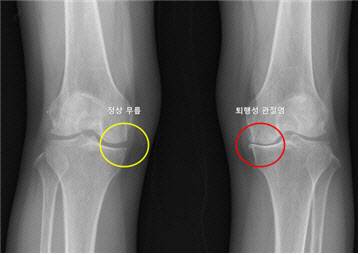

[이데일리 이순용 기자] 서울대병원 연구팀이 퇴행성 관절염 환자에서 반대쪽 무릎에 퇴행성 관절염이 발생할 가능성을 예측하는 머신러닝 기반 모델을 개발했다. 이번 연구는 두 개의 대규모 관절염 추적 연구 데이터를 기반으로 반대쪽 무릎에서의 병적 진행 가능성을 체계적으로 예측함으로써, 조기 개입을 통한 예방적 관리 전략의 길을 제시했다는 점에서 학술적 의의가 크다.

서울대병원 정형외과 노두현 교수팀(김지산 연구원)은 한쪽 무릎에 퇴행성 관절염이 있는 환자들을 대상으로 반대쪽 무릎에서 퇴행성 관절염이 발생할 가능성을 예측하는 머신러닝 모델을 개발했다고 9일 발표했다.